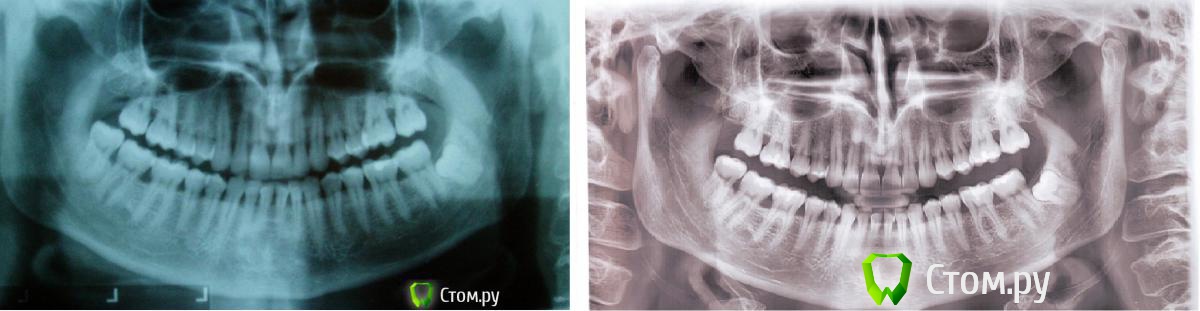

Ev127 Опубликовано 30 октября, 2014 Автор Поделиться Опубликовано 30 октября, 2014 Господа специалисты! Посмотрите пожалуйста динамику за год. Что скажете? Где-то стало хуже? Ссылка на комментарий